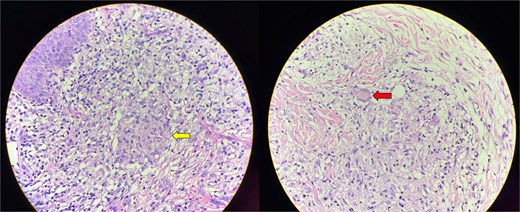

A 6.5-year-old boy presented in July 2024 with perianal skin lesions, scrotal and penile swellings and occasional passage of blood in stool for 1.5 years. On presentation, his height was 113 cm (between 10th and 25th percentile according to the Indian Academy of Pediatrics (IAP) charts), weight was 18.7 kg (between 25th and 50th percentile according to the IAP charts), and head circumference was 44 cm. On examination, he had microcephaly, hepatosplenomegaly, perianal erythematous plaques, and an erythematous swelling in the inguinoscrotal region (Fig. 1). Scrotal ultrasound showed diffuse scrotal wall edema with no funiculitis or epididymo-orchitis. Scrotal skin biopsy showed focal epidermal thinning and an epidermal neutrophilic infiltrate. Dermis and subcutaneous tissue showed an inflammatory infiltrate composed of lymphoplasmacytes and foamy macrophages, ill-defined granulomas with epithelioid-like cells, multinucleated giant cells and no evidence of necrosis (Fig. 2). Stool examination found eight erythrocytes/high power field (HPF) and 30 leukocytes/HPF. Stool calprotectin was 146 g/gm. Abdominal ultrasound showed hepatomegaly with coarse echotexture, splenomegaly, terminal ileal thickening (4.5 mm), and reactive subcentimetric mesenteric lymphadenopathy. Other investigations are shown in Table 1. Ileocolonoscopy showed caecal pitting and a solitary rectal ulcer which was excised by snare. Esophago-gastro-duodenoscopy found white spots in the duodenum. Colon biopsy showed mucosal ulceration, mixed inflammation in the lamina propria, crypt branching, cryptitis, few ill-defined epithelioid cell granulomas, and no evidence of necrosis (Fig. 3). Duodenal biopsy showed chronic lymphoplasmacytic inflammation in the lamina propria and maintenance of the crypt:villous ratio. Xpert MTB/Rif of the skin tissue, colon tissue, stool, and gastric lavage was negative. He received symptomatic treatment with oral colchicine, oral hydroxyzine, mupirocin ointment for local perianal application, fluticasone cream for scrotal application, and probiotics. At the 6-month follow-up, his inguino-scrotal swelling and perianal rash was persistent. The stool calprotectin in January 2024 was 716.46 g/gm. Repeat abdominal ultrasound showed mildly edematous bowel loops. Scrotal ultrasound in January 2025 showed diffuse chronic scrotal wall thickening with minimal edema and inflammatory changes. In view of the cutaneous histopathological findings, he was diagnosed with scrotal CD with indeterminate colitis and was started on oral immunomodulators and asked to follow-up after 1 month.

Skin biopsy showing an inflammatory infiltrate with lymphocytes, plasma cells and macrophages. Ill-defined, non-caseating granulomas with epithelioid cells are present (arrow in the first image). Langhans-type of multinucleated giant cells are seen (arrow in the second image).